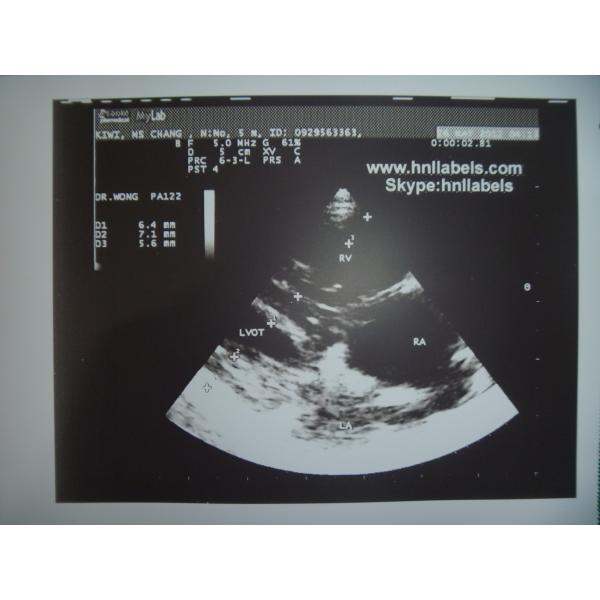

Ultrasonic Paper Compatible UPP-110s Medical Printing Media(Upp-110s Paper) Images |